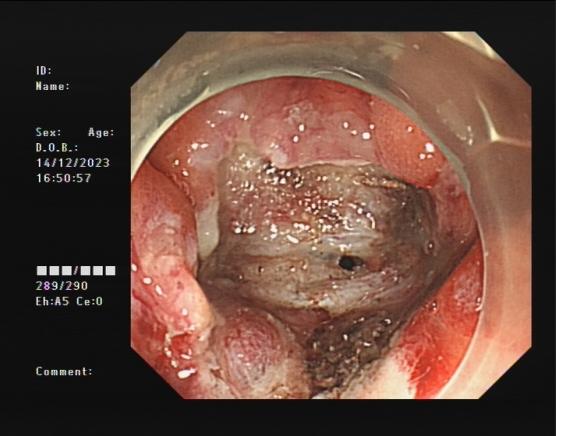

直腸側向發育性腫瘤 內鏡下黏膜下剝離術后創面

內鏡下黏膜剝離術(ESD):治療巨大平坦息肉,早期癌及癌前病變,黏膜下腫瘤等。